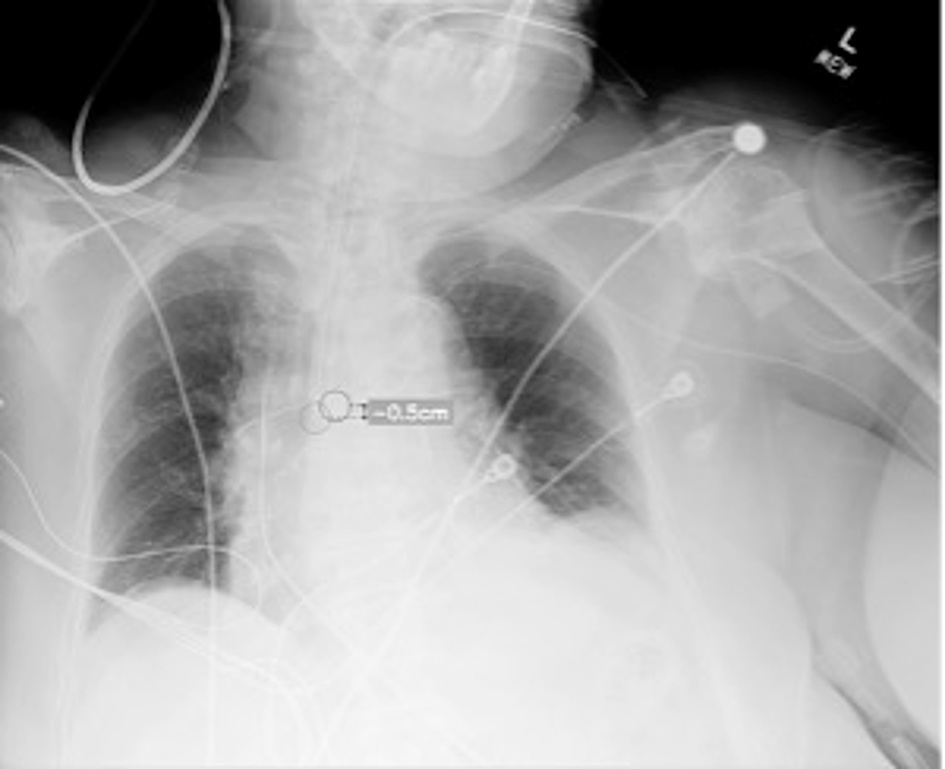

A slide presented by researchers at the ARRS meeting in Hawaii showed measurements used by an AI model for detecting correct endotracheal tube placements in x-rays of intensive care unit (ICU) patients. Image courtesy of Dr. Eui Jin Hwang.Tubes were malpositioned in 76 of the chest x-rays. In a comparison with an experienced thoracic radiologist and one trainee who independently evaluated the placements, the model achieved similar accuracy, the group found.

For deep malpositions of tubes, the model achieved an area under the receiver operating characteristic curve (AUC) of 0.96, and for shallow malpositions of tubes, the model achieved an AUC of 0.97, the researchers reported.